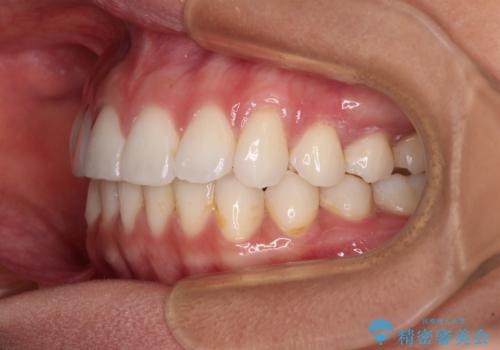

- 前に出ている上顎前歯が気になるとのことで来院された患者様です。

インビザラインを用い、IPR(歯と歯の間を削る)と歯列全体を後方に移動させることで、可能な限り前歯の突出感を改善することとしました。

元々の歯列も整っており、横顔の印象の出っ歯ではなかったため、仕上がりに満足できない可能性があると心配しておりましたが、口が閉じやすくなり、患者様には大変満足していただきました。